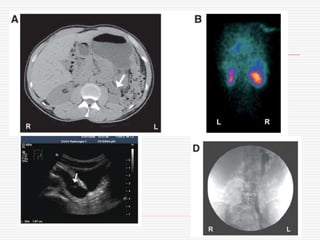

Graft dysfunction

1d post-

transplantation in

a 41 y-old

woman

5d post-transplantation

6d post-transplantation – sudden anuria and abdominal pain